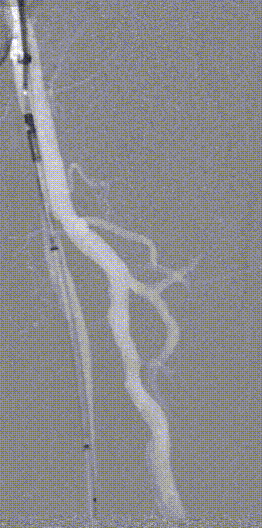

图为:血管准备:股浅旋切后球囊全程节段逐级式扩张

图为:评估血管准备:闭塞段残余狭窄90% ELUVIA全覆盖该区域病变

图为:股腘动脉DAART+区域性DES 最终造影